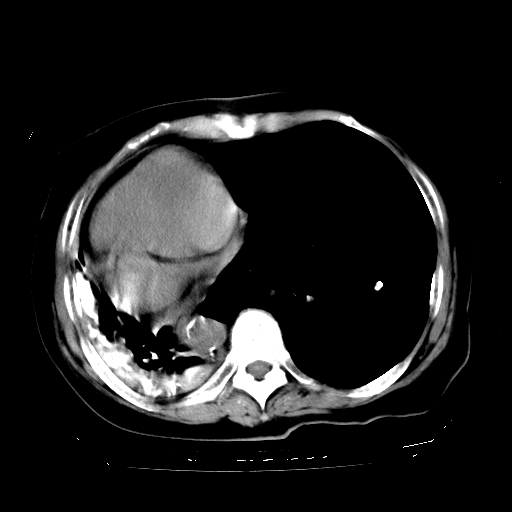

标题: CT23991:女,72岁,咳嗽、憋气一周。 [打印本页]

女,72岁,咳嗽、憋气一周,十年前曾患肺结核及胸膜结核。

1.右侧损毁肺伴胸膜钙化,2.左肺小结节灶,良性可能大,注意复查。3.肝脏左叶囊肿。4.先天性一侧肺不发育待出外(右侧胸廓无明显塌陷)。对比原片应该非常有帮助。